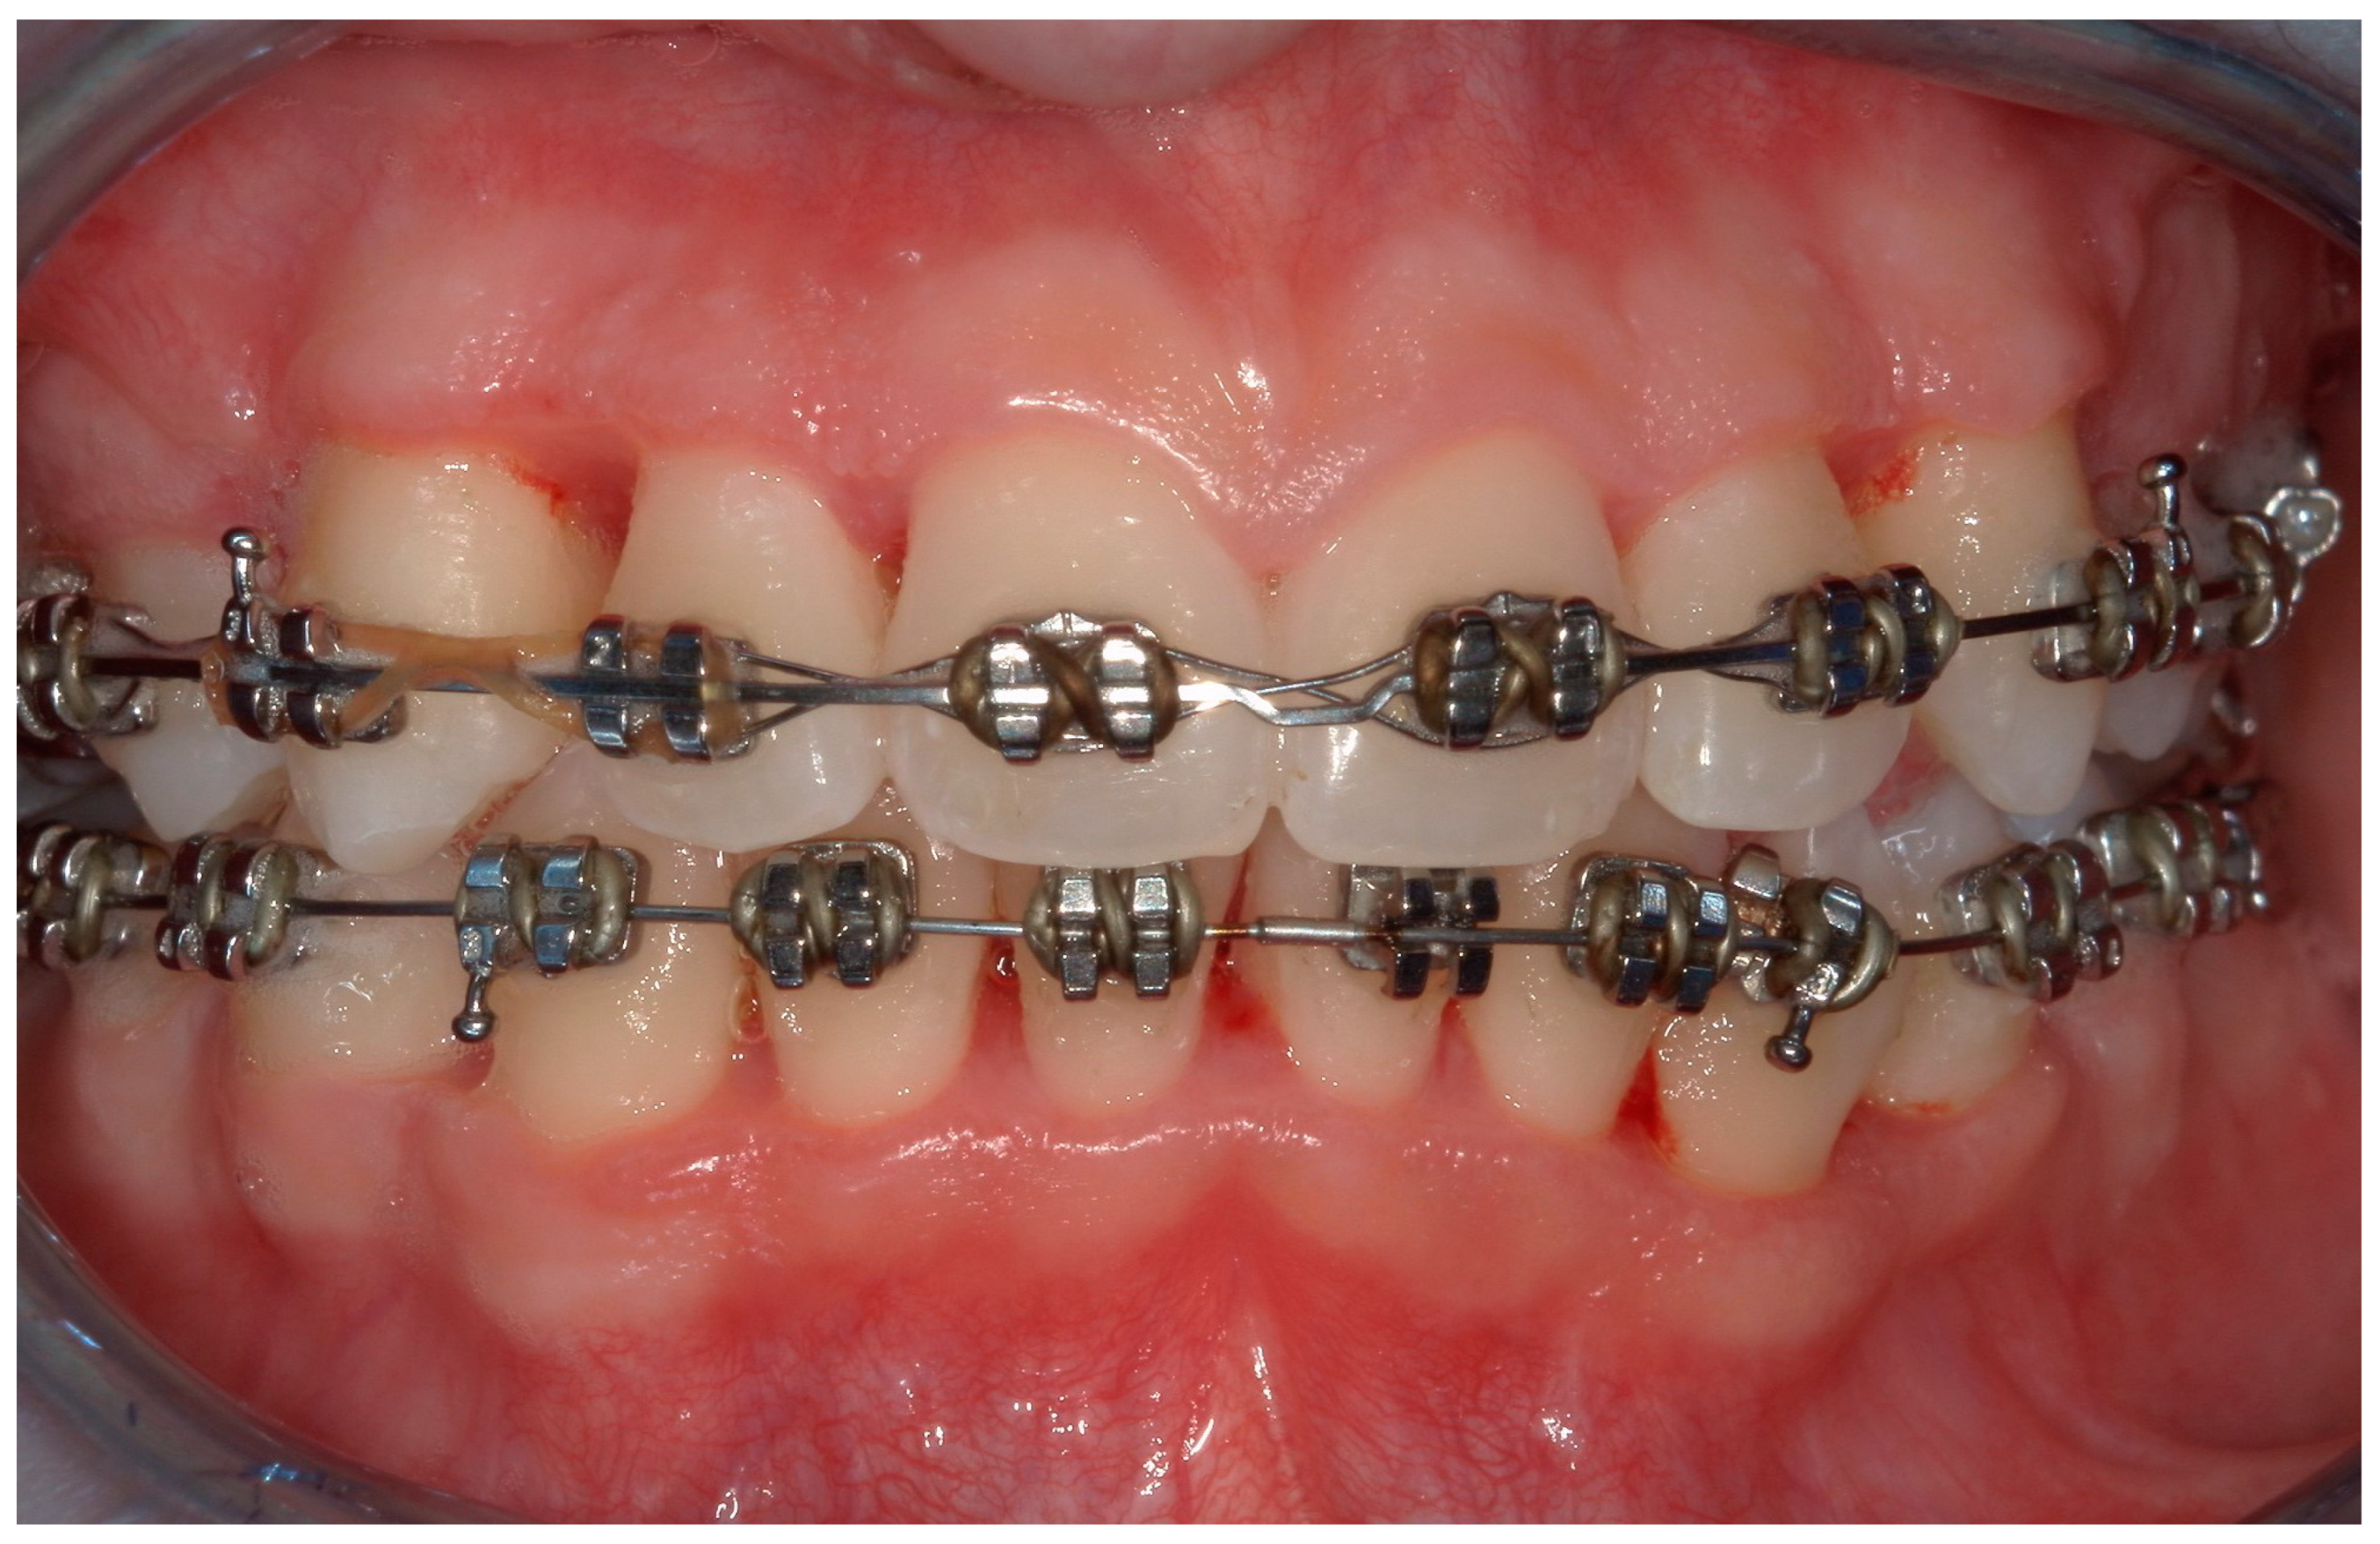

4.1. Case 1

4.2. Case 2